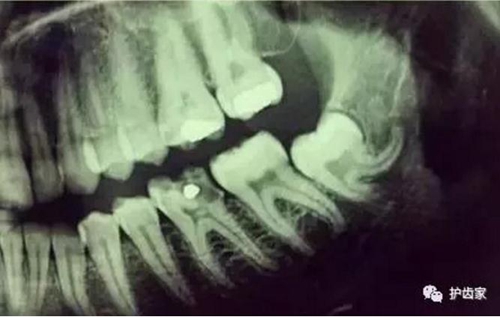

智齒周圍是牙槽骨,前面緊挨著第二磨牙,智齒下方大約兩三毫米遠(yuǎn)有一下頜神經(jīng)管,這神經(jīng)主要是下頜牙齒及下唇部位的知覺神經(jīng),一旦斷了,就會(huì)失去知覺。

根神經(jīng)線位置千變?nèi)f化,有些離智齒牙根很遠(yuǎn),有些很近,有些甚至穿過智齒根部。

拍片是為了了解智齒周圍情況,也是為了了解智齒結(jié)構(gòu),牙根結(jié)構(gòu)千變?nèi)f化,有可能是融合成一個(gè)根,也可能是八爪根。不同牙根不同位置及方向,只有通過拍片來確認(rèn)。

拍片也為了了解下頜神經(jīng)與智齒的關(guān)系,一般離得近,有醫(yī)療風(fēng)險(xiǎn)的,基本沒有醫(yī)生愿意拔,現(xiàn)在沒人為了幾百元,賠上自己的職業(yè)生涯。誰都怕拔智齒,敲打智齒,一不小心,碰到神經(jīng),就攤上大事了。有理都說不清。

通過拍片可以了解牙齒本身:生長方向,牙根數(shù)目,牙根是否彎曲,膨大等。

與重要解剖結(jié)構(gòu)的位置關(guān)系:如上頜磨牙與上頜竇的關(guān)系;下頜磨牙與下頜神經(jīng)管的關(guān)系;兒童在混合牙列期恒牙與乳牙胚的關(guān)系等。可以減少拔牙的風(fēng)險(xiǎn)。